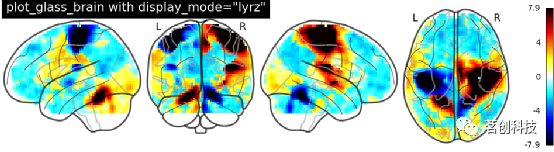

玻璃脑绘制:设置display_mode='lyrz'。

plot_glass_brain(

stat_img, threshold=0, colorbar=True,

title='plot_glass_brain with display_mode="lyrz"',

plot_abs=False, display_mode='lyrz'

)